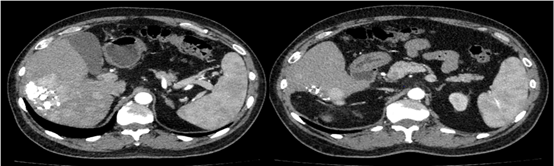

2019年1月17日(术后1个月)入院复查,影像学见疑似复发病灶。                         图片

图:影像学检查(2019-01-17)

遂予肝动脉化疗栓塞(TACE)治疗,行数字减影血管造影(DSA)可见肝右叶多个结节状肿瘤染色,明确肝左、右动脉分支为肿瘤供血动脉,判定为外科术后复发。